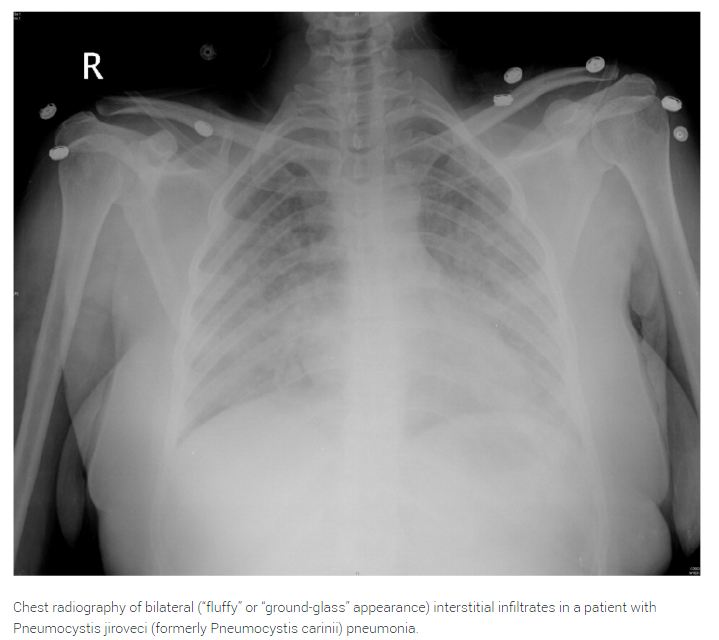

Pneumocystis jiroveci (formerly Pneumocystis carinii) pneumonia remains relatively common in patients with HIV infection, and may be the presenting manifestation of HIV in patients who have not yet been diagnosed. Patients with P. jiroveci pneumonia classically present with fever, progressive exertional dyspnea, and nonproductive cough. Although there are a wide variety of radiologic findings, chest radiography typically shows bilateral interstitial infiltrates.

Empiric treatment is appropriate in patients with mild, classic symptoms and CD4 lymphocyte counts of 200 per mm3 (0.20 × 109 per L) or less. However, further diagnostic techniques (e.g., induced sputum examination, transbronchial biopsy with or without bronchoalveolar lavage) should be used if patients do not improve after four to five days of empiric therapy. Severe pneumococcal pneumonia and infections caused by atypical organisms (i.e., Legionella species) or other opportunistic pathogens should also be considered, depending on CD4 lymphocyte counts and geographic location.